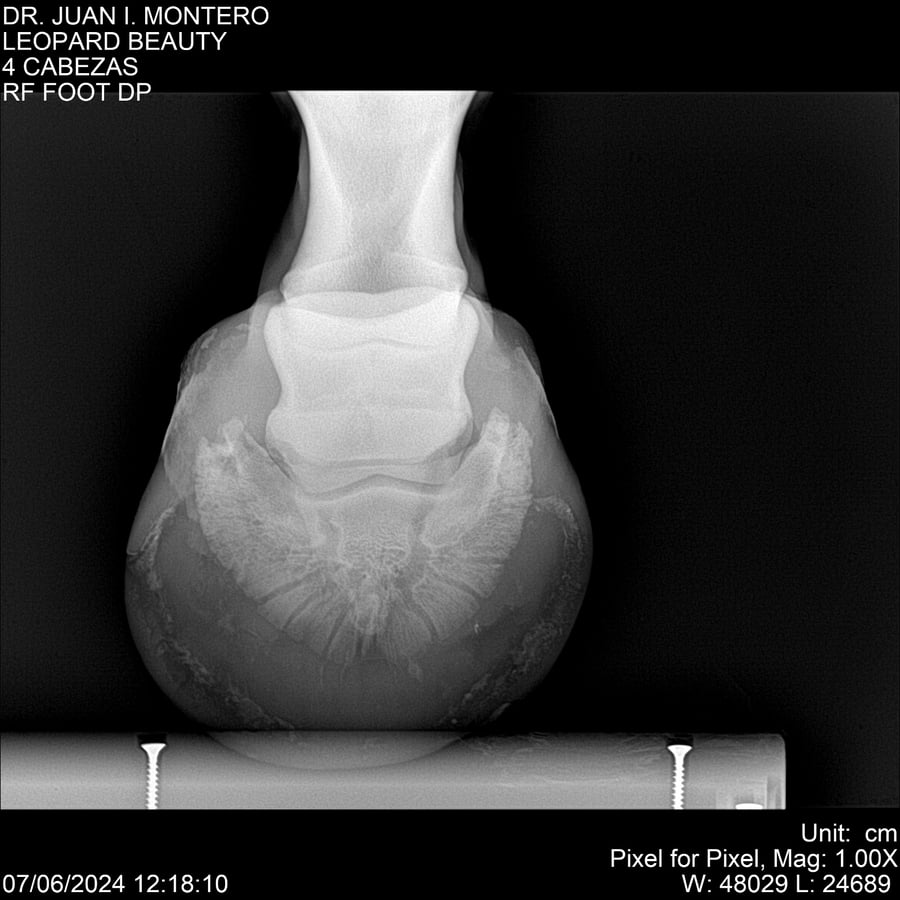

LOTE 16, LEOPARD BEAUTY Lote Anterior Volver al remate Lote Siguiente Ficha Contacto Montevideo - Ficha del Lote Identificador: #281095 Categoría: Yeguarizos Montevideo - 50 Visualizaciones ClicData Contacto Empresa: Abelenda N. R., Walter Hugo Nombre*: Teléfono* : E-mail* : Mensaje Enviar Registrese gratis Este contenido Exclusivo está disponible sólo para usuarios registrados Ingresar